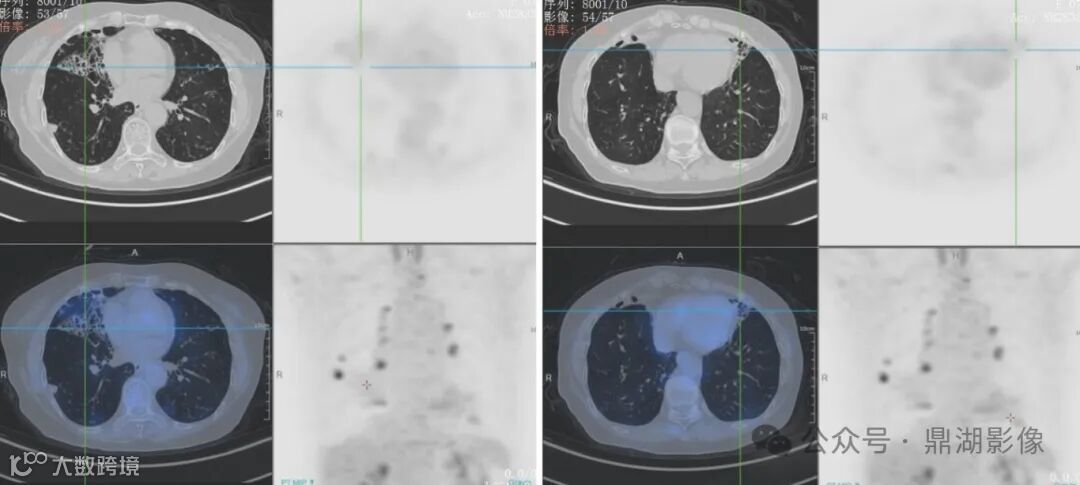

双肺多发支气管扩张伴感染,以右肺中叶、左肺上叶下舌段为著;余双肺散在多发小结节、小结片及小斑片影,部分代谢轻度增高,考虑感染性病变;

双肺门多发淋巴结,代谢异常增高,考虑淋巴结炎。

支气管扩张及结节为主型病变:以支气管扩张伴周围小叶中心结节为主,可合并空洞、斑片影等其他征象,表现为树芽征的细支气管炎、支气管管壁增厚的节段性支气管扩张及伴有黏液堵塞是疾病活动的表现。右肺中叶、左肺舌段是 NTM 患者支气管扩张累及的常见部位

NTM与肺结核的CT征象有一定相似性,但仍有其特征表现。NTM双肺病变比肺结核要常见,前者更容易出现薄壁空洞 (直径>3 cm) 和支气管扩张,且支气管扩张好发于右肺中叶和左肺上叶舌段

NTM行FDG显像一般代谢轻度增高;结核性肉芽肿FDG显像常显示代谢异常增高